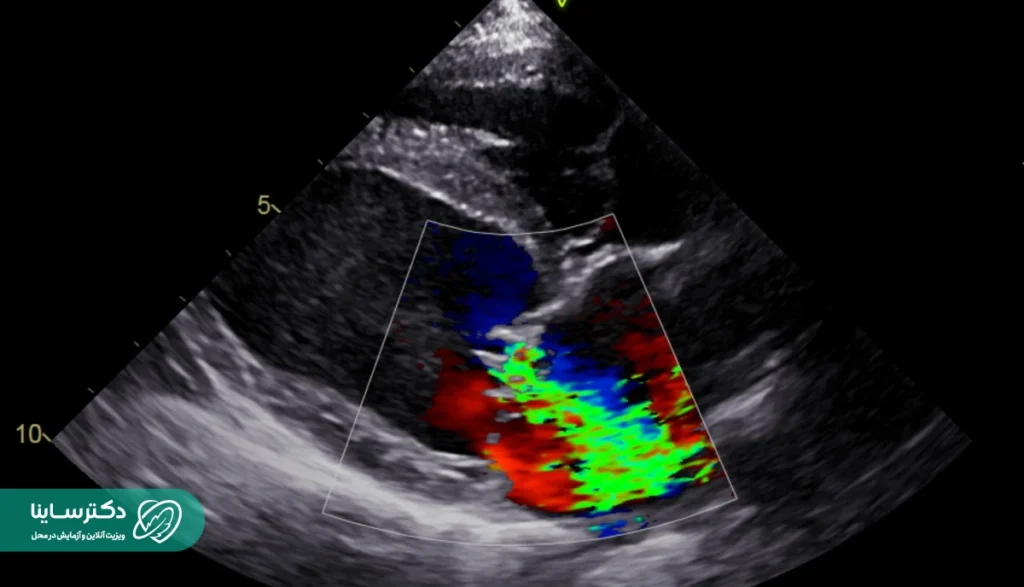

اکو داپلر

سونوگرافی داپلر (Doppler Echocardiogram) یا اکو داپلر تکنیکی است که سرعت و جهت جریان خون در قلب و رگهای خونی را اندازهگیری میکند. این دستگاه هم با امواج صوتی کار میکند. این امواج وقتی به سلولهای خونی برخورد میکنند زیر و بمی صدا را تغییر میدهند. با این روش پزشک میتواند درک کند که آیا دریچههای قلب مسدود شدهاند یا نشتی دارند. سیگنالهایی که داپلر تولید میکند، میتواند به پزشک در بررسی میزان فشار خون در شریانهای قلب کمک کند.

اکو داپلر رنگی

این تکنیک برای نشاندادن جریان خون بهصورت رنگی کاربرد دارد و برای برجستهکردن جهات مختلف جریان در قلب از رنگهای مختلفی استفاده میکند. با اکو داپلر رنگی پزشک میتواند نشتی دریچههای قلب و هرگونه تغییر دیگر در جریان خون را بسیار راحتتر تشخیص دهد.